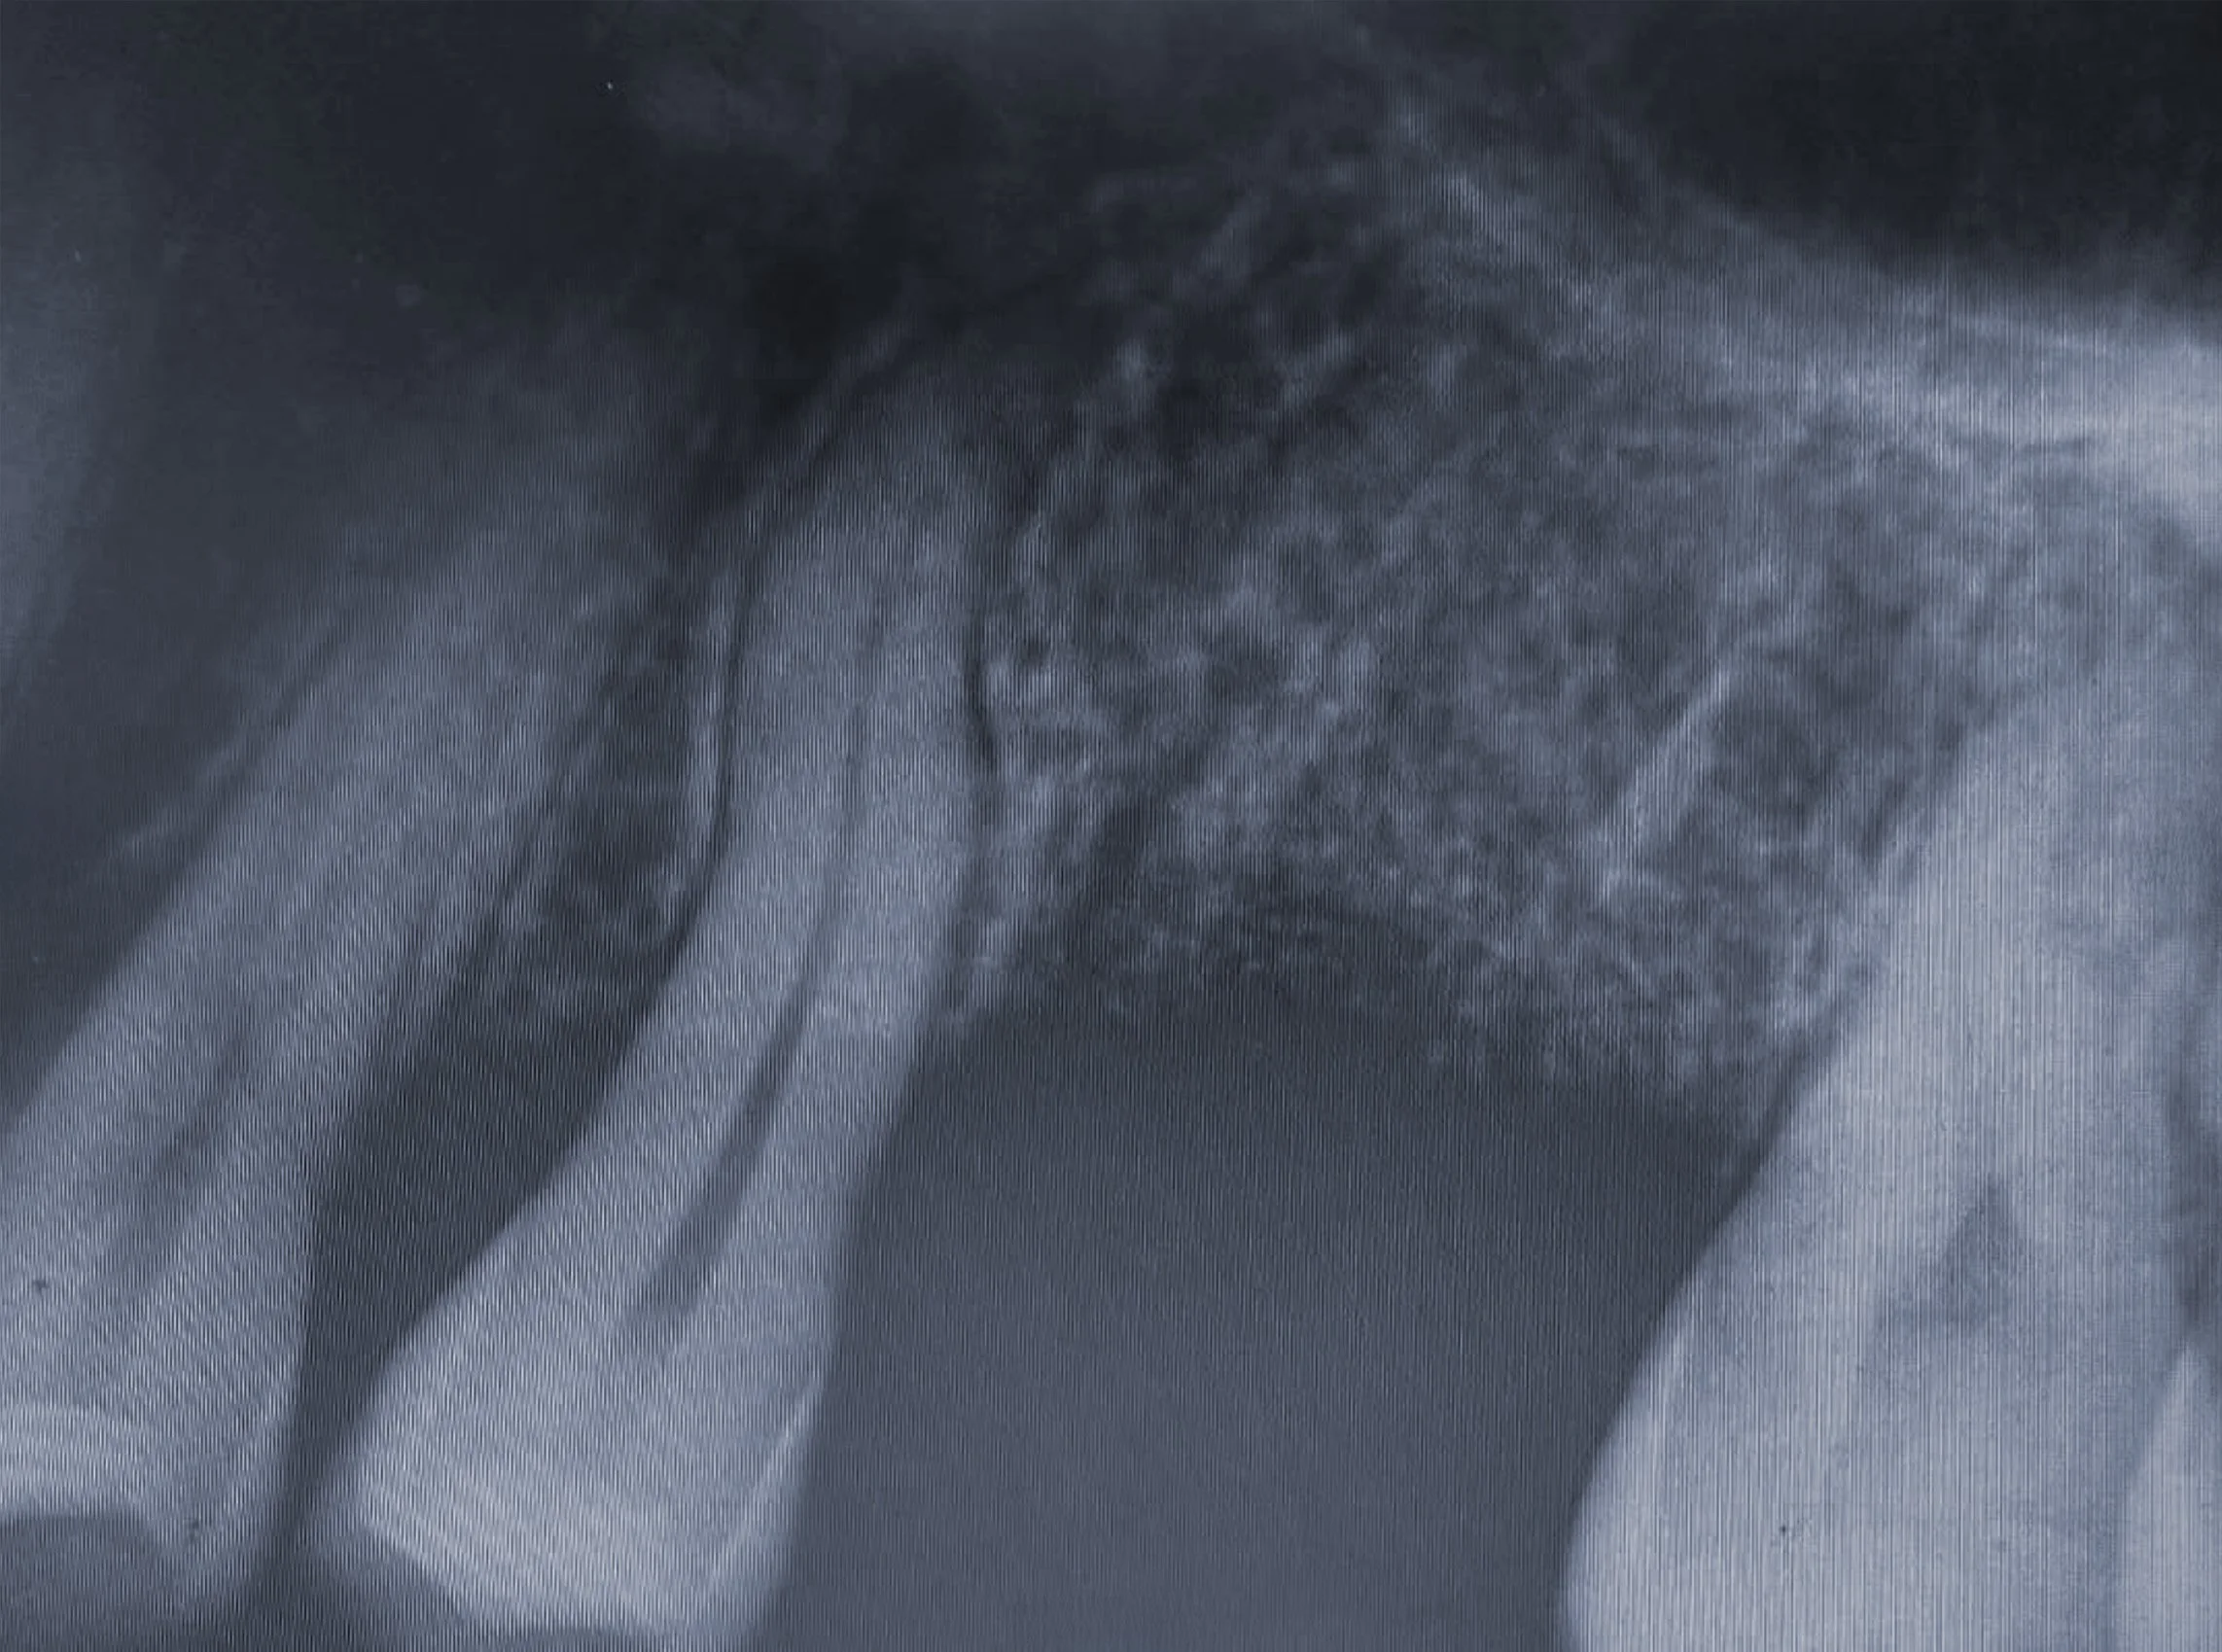

Step 1 — Extraction & Ridge Preservation

The tooth was removed atraumatically, and a bone graft with a resorbable membrane was placed to maintain ridge contour and volume for future implant placement.